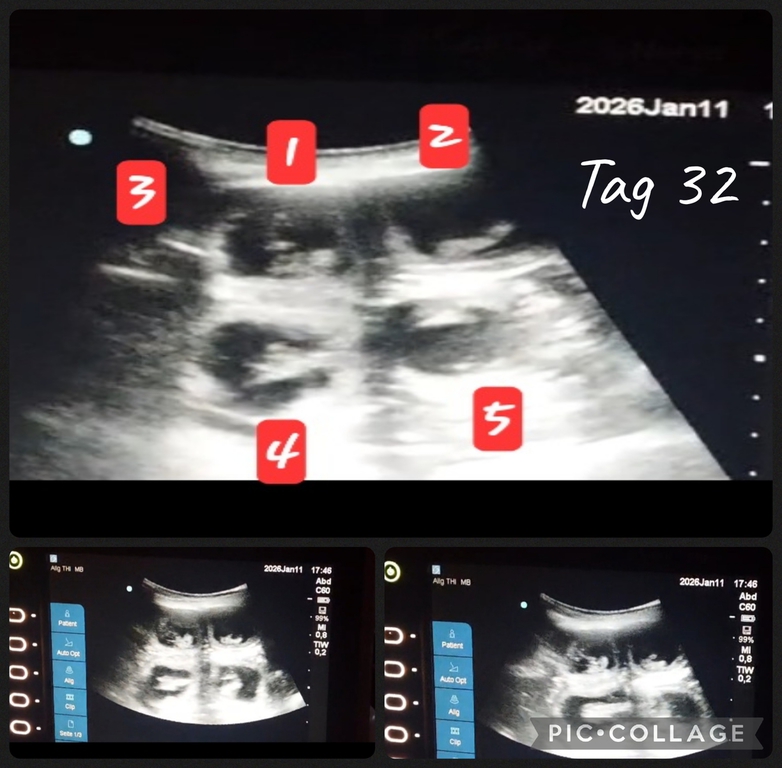

Tragbares Ultraschall

Seid Sonntag sind wir wieder glückliche Besitzer eines Ultraschallgerätes. Ein wunderbares leichtes und auch tragbares US. Durch liebe Menschen hatten wir glück dieses noch nicht so alte Ultraschallgerät zu bekommen. (War vor kurzem noch im Einsatz im KH Notaufnahme). Danke Pelin & Hanno